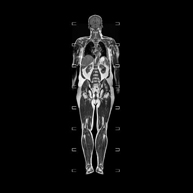

Prueba diagnóstica no invasiva que consiste en la obtención de imágenes de alta definición anatómica de la glándula prostática mediante el empleo de un campo electromagnético y ondas de radio (con un emisor y un receptor). No utiliza radiación ionizante. Se utiliza una bobina endorrectal para obtener imágenes de máxima definición anatómica de la próstata, que permitirá realizar el estudio espectroscópico (estudio a nivel molecular que ayuda a diferenciar las células de origen maligno o tumoral). También se realiza el estudio con contraste paramagnético que aporta una mejor definición tisular. Esta prueba dura unos 40 minutos, durante los cuales el paciente deberá estar lo más quieto posible. Como preparación previa requiere limpieza del colon. Esta prueba está especialmente indicada en aquellos pacientes con sospecha de neoplasia de próstata, con neoplasia de próstata conocida para el estadiaje tumoral, estudio de localización del tumor prostático como guía o mapa para la biopsia, seguimiento de los pacientes con neoplasia de próstata tratados con tratamiento quirúrgico o radioterápico, sospecha de recidiva de la neoplasia de próstata, etc. - RM Cuerpo entero (Total body)

Prueba diagnóstica no invasiva que consiste en la obtención de imágenes de alta definición anatómica de todo el cuerpo mediante el empleo de un campo electromagnético y ondas de radio (con un emisor y un receptor). No utiliza radiación ionizante. Es una prueba muy importante en la búsqueda de metástasis en pacientes con neoplasia conocida. No requiere preparación previa. No es necesario el empleo de contraste paramagnético (Gadolinio). - Angio-RM Aorta abdominal